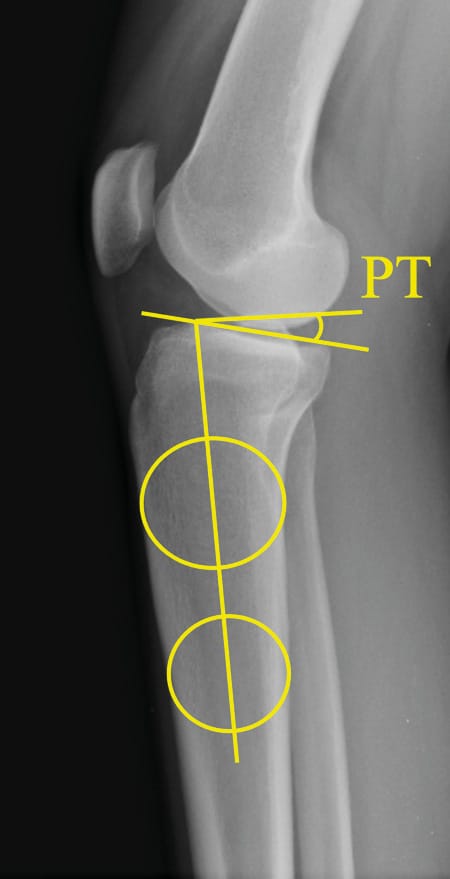

Radiology images should be obtained to include true lateral views showing 15 cm of proximal tibia with 20° of flexion in single-leg weight-bearing. The condyles will be aligned under fluoroscopy before the conventional radiography is performed. Any deviation from lateral will lead to distortions and the measurements will not be possible to interpret [14] Vieider RP, Mehl J, Rab P, Brunner M, Schulz P, Rupp MC, et al. Malrotated lateral knee radiographs do not allow for a proper assessment of medial or lateral posterior tibial slope. Knee Surg Sports Traumatol Arthrosc. 2024;32(6):1462–9. (Figure 1). Next, the technique for measuring the tibial slope must be chosen so that it is reproducible and can be compared from one study to another. It is crucial to choose one method and stick to it. The technique that uses the proximal anatomical tibial axis has a normal value of 9° of slope and the method is described in Figure 2 [15] Brazier J, Migaud H, Gougeon F, Cotten A, Fontaine C, Duquennoy A. Evaluation of methods for radiographic measurement of the tibial slope. A study of 83 healthy knees. Revue de chirurgie orthopédique et réparatrice de l’appareil moteur. 1996;82(3):195–200. . The normal value for SATT is 1.31 mm [16] Cance N, Dan MJ, Pineda T, Demey G, Dejour DH. Radiographic Investigation of Differences in Static Anterior Tibial Translation With Axial Load Between Isolated ACL Injury and Controls. Am J Sports Med. 2024 Feb 1;52(2):338–43. . If translation is posterior, the measurement will have a negative value. The measurement method is described in Figure 3.